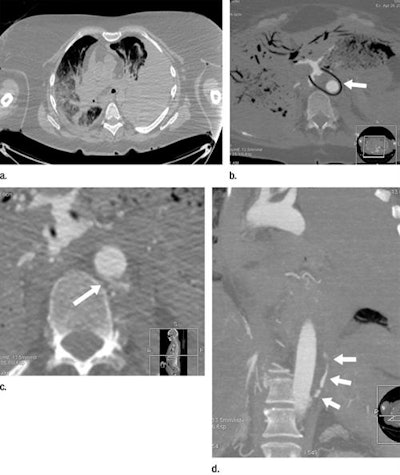

CT angiography might be able to help. In prior research, Grabherr and colleagues demonstrated the potential of using CT angiography instead of standard CT to improve the postmortem visualization of vascular lesions in a small sample population. Their protocol used a pressure-controlled perfusion device (Virtangio, Fumedica) to inject a mixture of paraffin oil and a contrast agent (Angiofil, Fumedica) into the femoral vasculature -- ultimately enabling the visualization of arteries and veins during CT angiography. They suggested that this enhanced imaging could help guide and optimize subsequent autopsy.

Postmortem CT angiography revealed a greater number of findings than conventional autopsy did, even when the cases were divided by type of wound. And this difference was especially pronounced for skeletal and vascular lesions, many of which were not even visible during autopsy.

The radiologist and forensic pathologists detected a statistically significant increase in essential bone and vascular findings using CT angiography compared with autopsy for all of the causes of death (p < 0.001). Specifically, CT angiography led to the discovery of 11.5% more essential vascular lesions in cases of natural death, 39.1% more in cases of localized trauma, 29.9% more in cases of suspected medical error, and 31.4% more in cases of polytrauma.